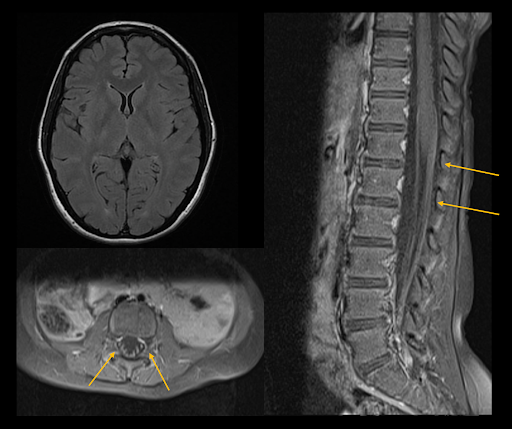

Bildgebung: MRT des Kopfes und der Wirbelsäule

- FLAIR-Sequenz des Neurokraniums: Unauffällig.

- T1 post-KM der Wirbelsäule axial und sagittal: kräftige Kontrastmittelanreicherung des conus medullaris sowie der Nervenwurzeln der cauda equina.